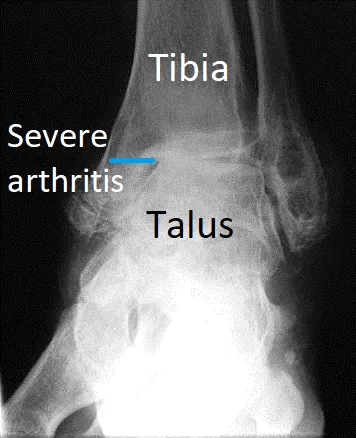

Ankle Fusion (Ankle Arthrodesis)

Ankle fusion is permanently stiffening the bones of the ankle together with plates and screws. This procedure is also known ankle arthrodesis.

The aim of fusion is to improve pain and function by removing arthritis and joint instability. It is only recommended after non-surgical treatment has failed to improve symptoms.

A simple way of thinking about fusion is "turning a painful and stiff joint into just a stiff joint".

Most ankle fusions are for arthritis and deformity. A few are done for severe joint instability when no other treatment works.

Fusion is still the best way of treating severe ankle arthritis when there is bone loss, deformity and/or instability. It is also the correct procedure in most people under 60 years of age.